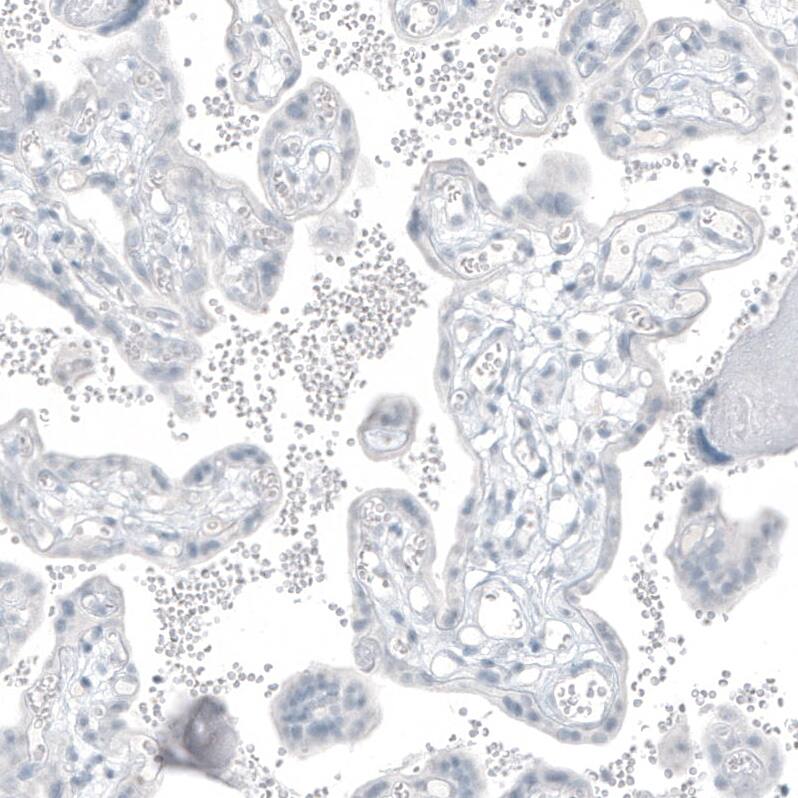

Staining of human placenta shows no positivity in trophoblastic cells as expected.